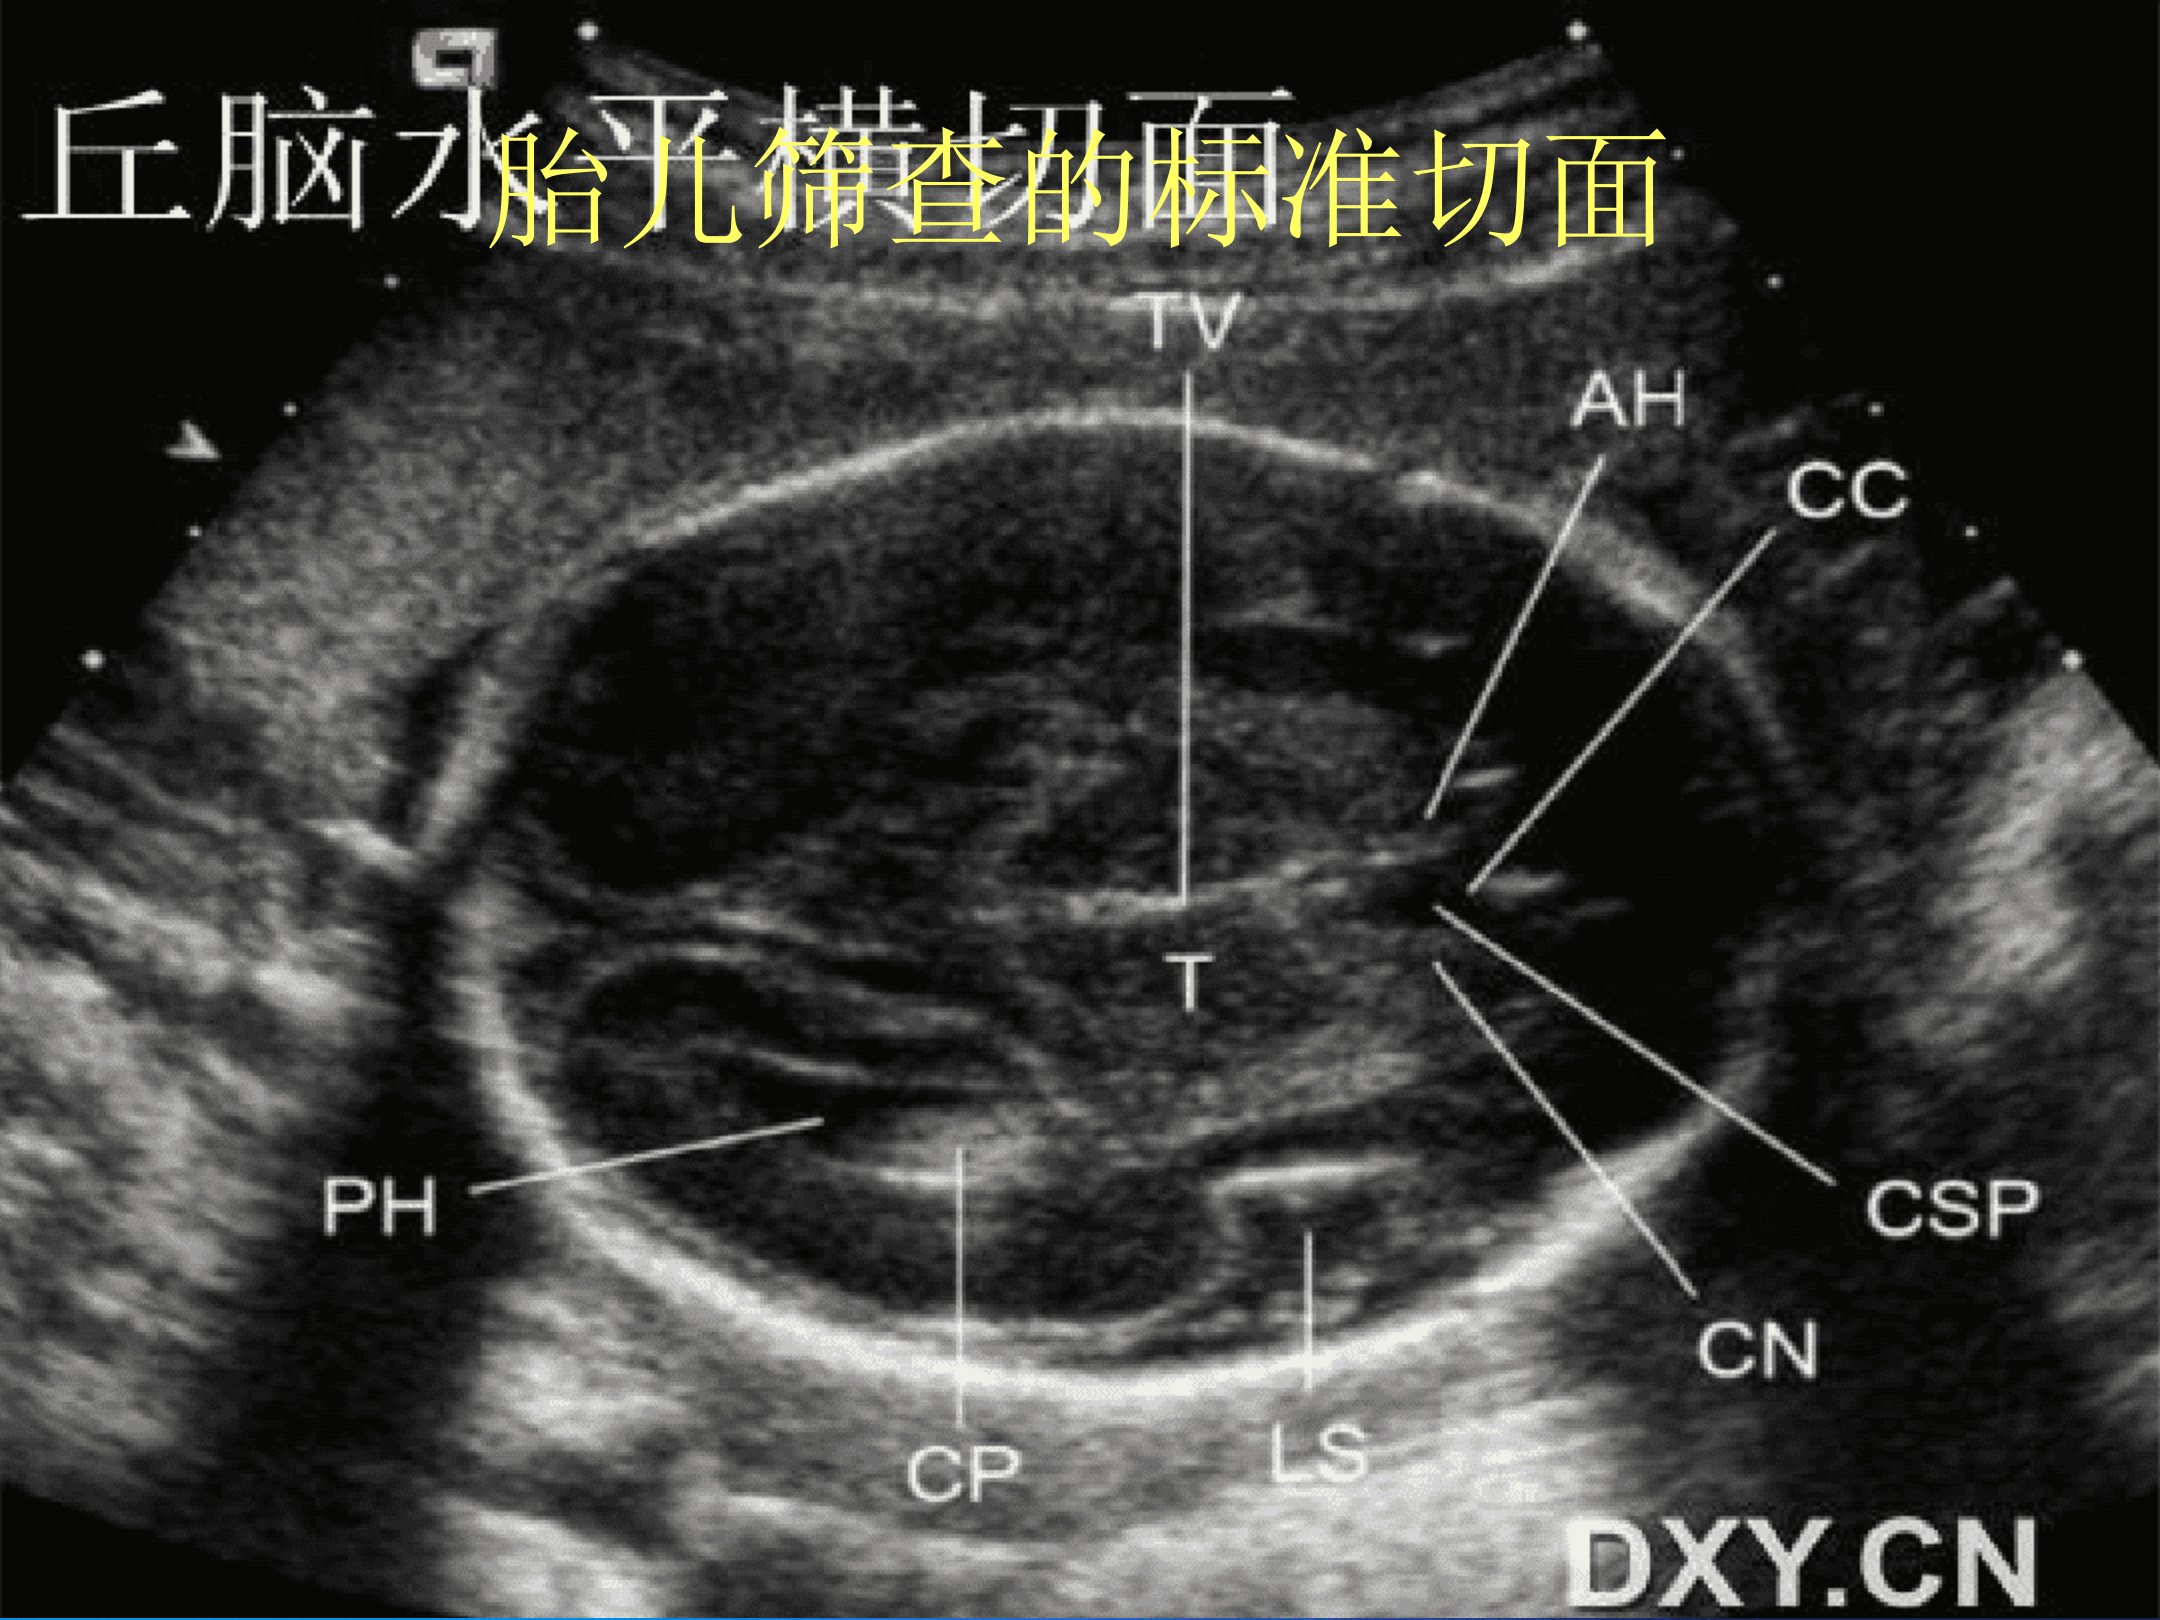

胎儿筛查超声标准切面及测量包括多个关键切面。丘脑水平横切面需显示脑中线、透明隔腔、两侧丘脑及第三脑室BPD测量要求超声束与脑中线垂直可发现无脑儿、脑膜脑膨出等畸形。侧脑室水平横切面扫查时声束平行向胎儿头顶部移动可显示侧脑室后脚及脉络膜。小脑水平横切面要求同时显示清晰的小脑半球、透明隔腔可测量小脑横径等。双眼球水平横切面需显示双侧晶状体和眼球可诊断小眼畸形、无眼畸形等。四腔心平面是最重要的心脏切面可观察心脏大小、方位、结构和功能能诊断左、右心发育不良等心脏畸形。胎儿腹部横切面用于腹围测量。此外还介绍了胎儿常见畸形包括中枢神经系统畸形(如脑积水、蛛网膜囊肿)、面部畸形(如唇裂及腭裂)、胸部畸形(如膈疝、左心发育不良)以及腹部畸形(如十二指肠闭锁、腹裂、脐膨出)等。